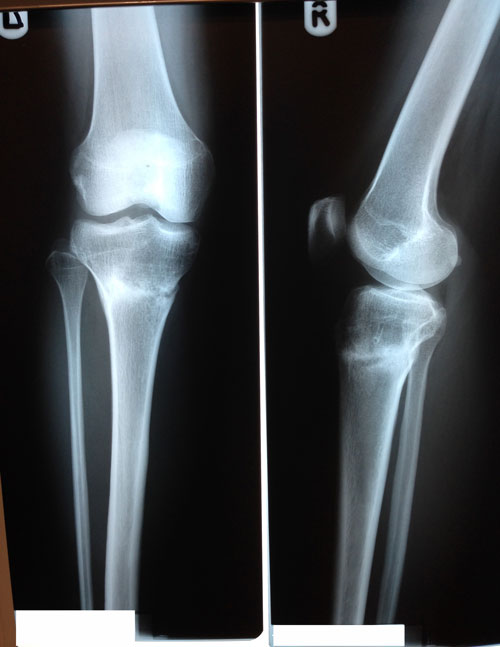

Дата снятия аппаратов 06.11.02013г.

Срок лечения 107 дней.